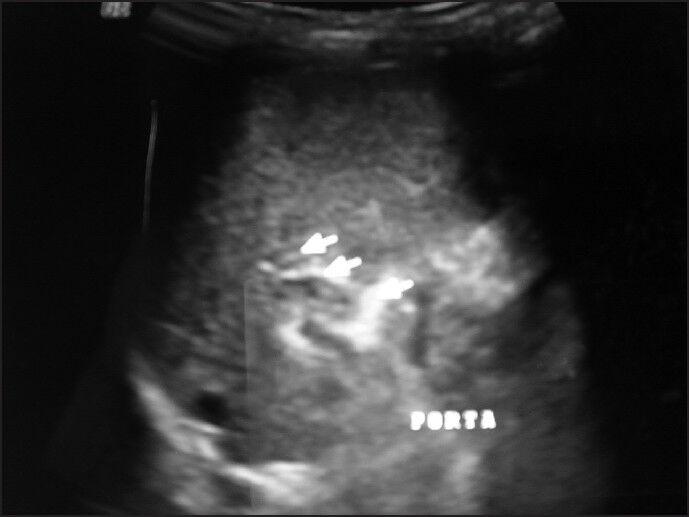

Extrahepatic portal vein obstruction (EHPVO) is the commonest cause of portal hypertension presenting with gastrointestinal bleeding and splenomegaly. Medical management of this condition may provide relief, but involves repeated hospital visits and endoscopic procedures. Surgery is an effective curative solution by lowering portal venous pressure with effective shunting of venous blood from splanchnic to systemic circulation. Shunt surgery for such a small baby has not been previously reported and splenectomy has its own problems. Similarly, banding or sclerotherapy in such babies is not without risk. Among the various shunt options, Mitra shunt (spleen preserving, side-to-side lienorenal shunt), developed and standardized in our own country, stands out as the most optimum surgical treatment for EHPVO in early infancy. We report a 4-month-old baby, youngest recipient of Mitra shunt reported in literature with successful outcome.

https://cdn.ncbi.nlm.nih.gov/pmc/blobs/7af7/3983775/e9ece062e21f/JIAPS-19-96-g001.jpg